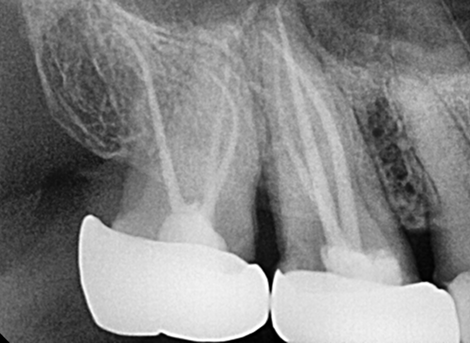

Complete disinfection of the root canal.

Laser Cleaning